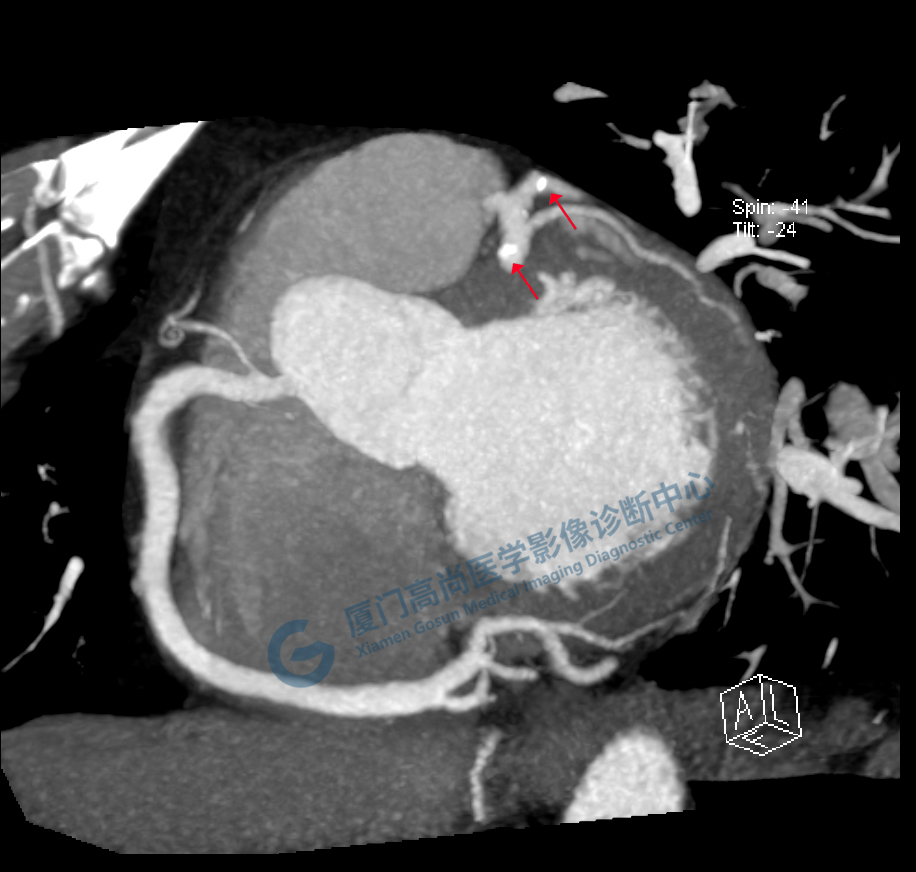

通過(guò)冠脈CTA三維重建,可以再現(xiàn)冠狀動(dòng)脈的形態(tài)、走行,從中了解冠脈的通暢情況。當(dāng)出現(xiàn)冠狀動(dòng)脈粥樣硬化時(shí)(如下圖所示),我們可以看到冠脈的管壁變厚了,并且出現(xiàn)了鈣化斑塊及部分軟斑塊、管腔不均勻的變窄現(xiàn)象。一般當(dāng)出現(xiàn)重度狹窄(狹窄程度>75%)時(shí)便需要進(jìn)行積極的臨床干預(yù)。(左圖為重度狹窄的前降支,黃箭為鈣化,紅箭為軟斑塊、重度狹窄部位,而右圖為正常的左冠前降支)。

圖像所見(jiàn):左冠狀動(dòng)脈前降支,前降支近段可見(jiàn)局部鈣化斑塊,管腔狹窄約5%,左側(cè)冠狀動(dòng)脈對(duì)角支可見(jiàn)鈣化斑塊,管腔狹窄約20%-30%。

左冠狀動(dòng)脈回旋支,近段可見(jiàn)局部鈣化斑塊,管腔狹窄約5%-10%。

影像診斷:CAD-RADS分級(jí):2(25%-49%),輕度狹窄。